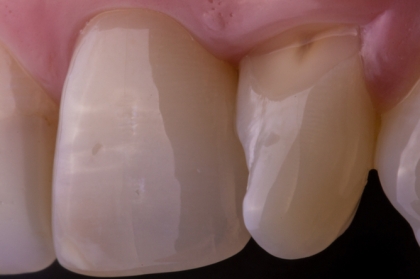

O autor pretende ao longo da apresentação demonstrar os aspetos que, na sua opinião, são os mais relevantes para se atingir sucesso estético nas restaurações diretas em dentes anteriores na prática clínica diária.

- Seleção de cor segundo croma e valor das resinas.

- Importância do valor na integração das restaurações.

- Técnicas estratificada/monoshade.

- Restauração do bordo incisa